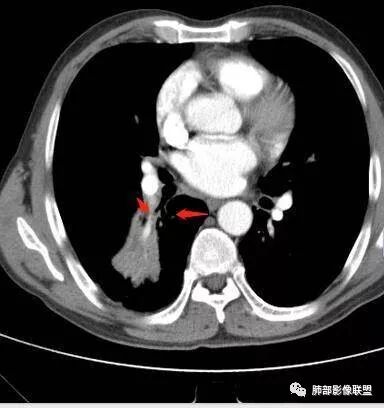

南边:这个肺门区,11区和7区都有一些淋巴结,淋巴结的形态不是类圆形,而是梭形的。这个病灶给的图比较少,个人倾向,第一强化非常均匀,肉芽肿性病变;第二,里面血管走行非常自然,远端大近端小,倾向炎性,特别是下面还有斑片状影,非阻塞远端,支气管远端病灶下叶背段,其他段也有,所以我倾向炎性;另外,它里面整个走行符合支气管树爬行征,我倾向结核可能,首先我定在炎性,其次有没有结核的可能。

右肺下叶背断肿块,外围大,内带相对狭长         远端有膨隆,边缘模糊、凹凸不平         血管走形自然,病灶近端支气管通畅,沿支气管树蔓延         周边有多发病灶,多为磨玻璃密度且边界不清。